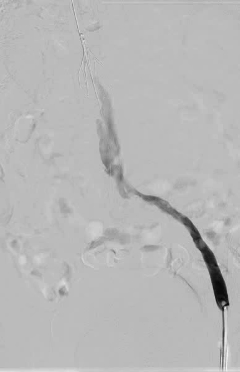

多学科会诊后,结合患者实际情况,田轩院长带领团队制定了双侧髂静脉血管球囊扩张成形 + 经皮机械血栓清除术 + 下腔静脉球囊扩张成形术的诊疗方案。

手术在 DSA 引导下开展,团队按照既定方案规范操作,小心清除滤器周围血栓,重建静脉通道,全程注重操作精准性与安全性,手术顺利完成。